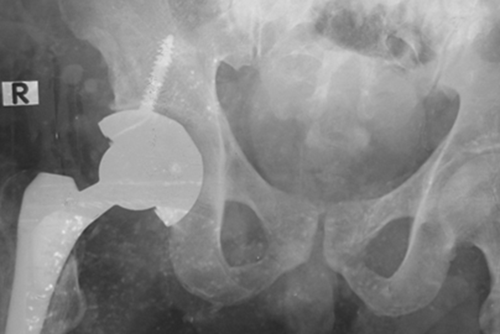

හමුදා වෙඩිතැබීමෙන් උකුල් ඇටයට හානි සිදුවී ඇති මෙලන් පෙරේරා

උකුල් ඇටයට ඇනයක් දමා බද්ධකර ඇතඅපි පහත සඳහන් නිගමන ඔබ වෙත ඉදිරිපත් කරමු: